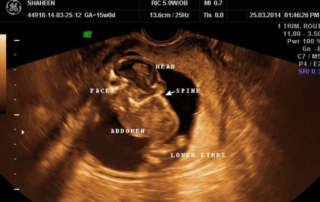

Antenatal ultrasound diagnosis of ‘Iniencephaly Apertus’

DOI: 10.36205/trocar1.2021006